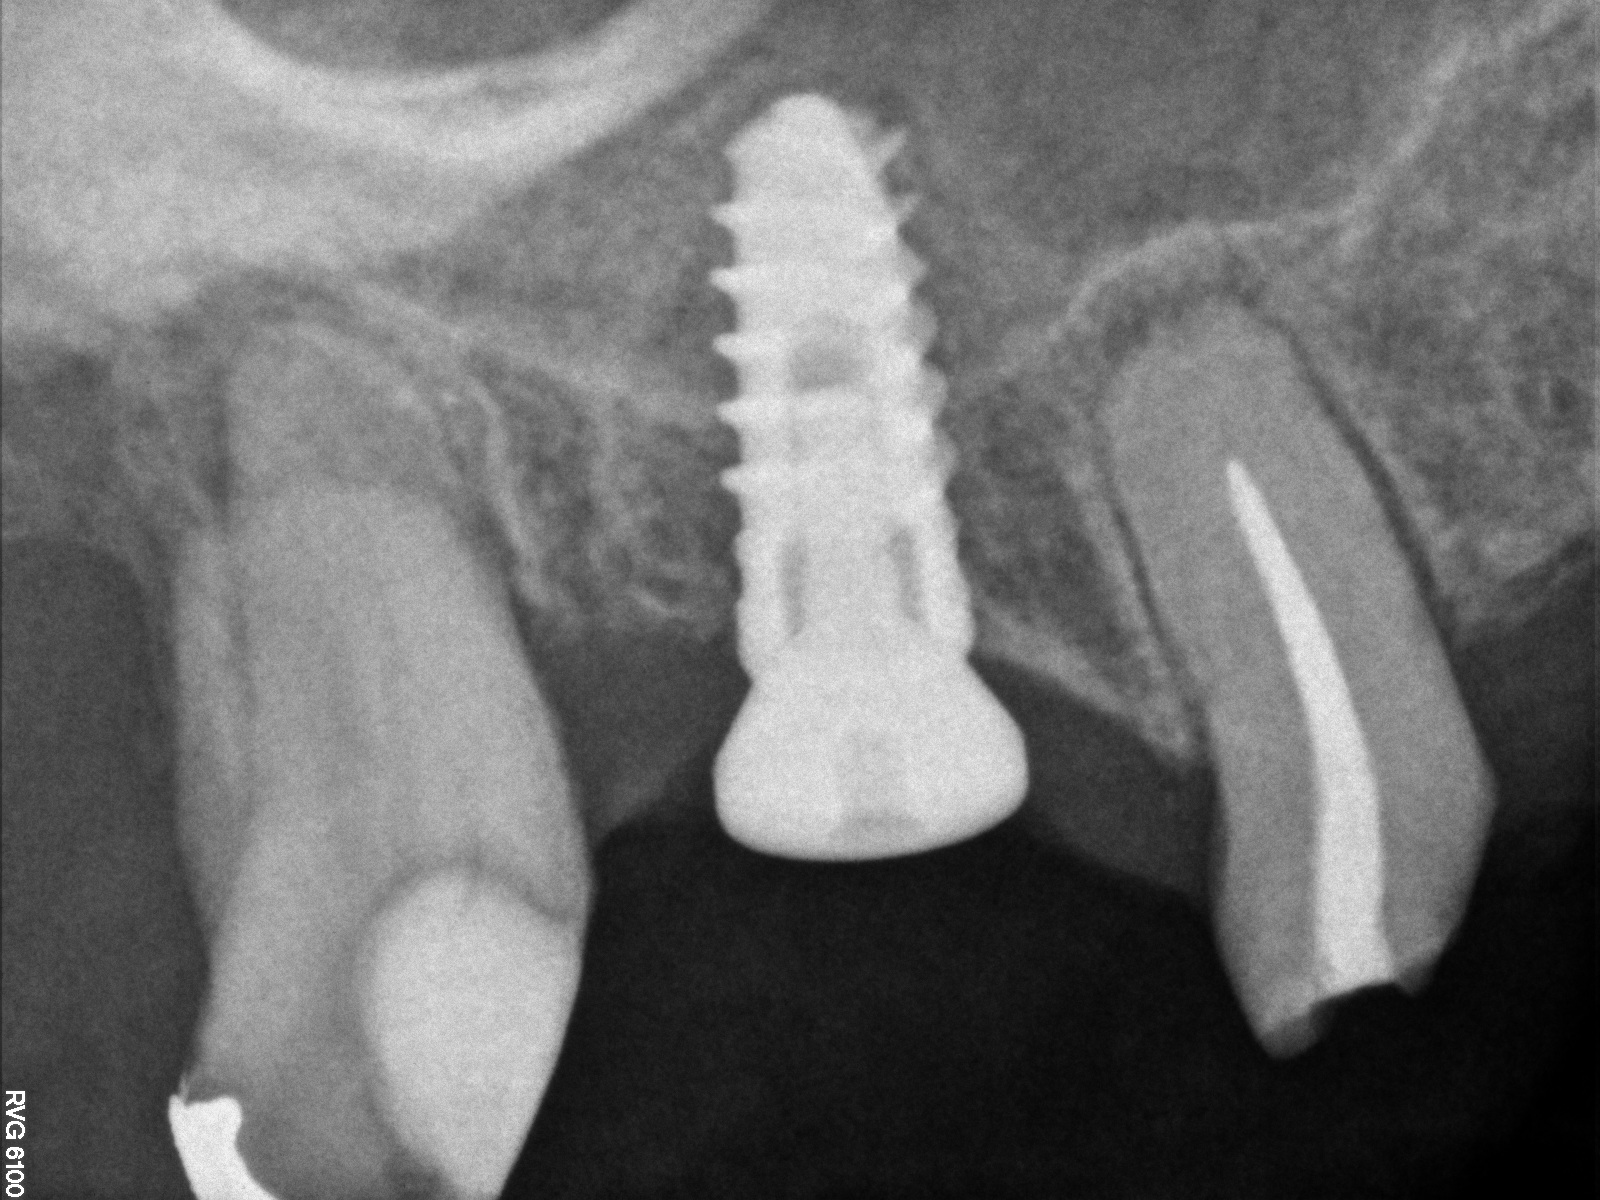

Day of sinus augmentation and implant placement in the No. 3 position. The sinus membrane has been raised about 7 mm to 8 mm.

Fig. 21

CBCT scan (Kodak 9000D) of No. 3 area, day of placement. Appearance of native bone and bone graft is clearly discernable.

Fig. 22

A 6.5-month postoperative radiograph. Teeth Nos. 2 and 4 have been extracted and an immediate implant had been placed in the No. 4 position.

Fig. 23

This patient was a 73-year-old man with only about 3.5 mm of native bone in the No. 3 site (Figure 20). The composite graft used here was a 50:50 mixture of DFDBA and deproteinized bovine bone mineral (Osteohealth, www.osteohealth.com) with approximately 40% calcium sulfate added. The implant was the same type and length as in Case 1 above. Figure 21 shows the area on the day of placement. In the CBCT scan on the day of placement (Figure 22), the native bone and bone graft were clearly discernable. However, the postoperative radiograph taken at 6.5 months (Figure 23) showed no marginal bone loss and a significantly denser appearance than when the graft was place. The membrane was raised about 7 mm to 8 mm. The final radiograph was taken after extraction of tooth No. 2 and after extraction of tooth No. 4 and immediate implant placement.